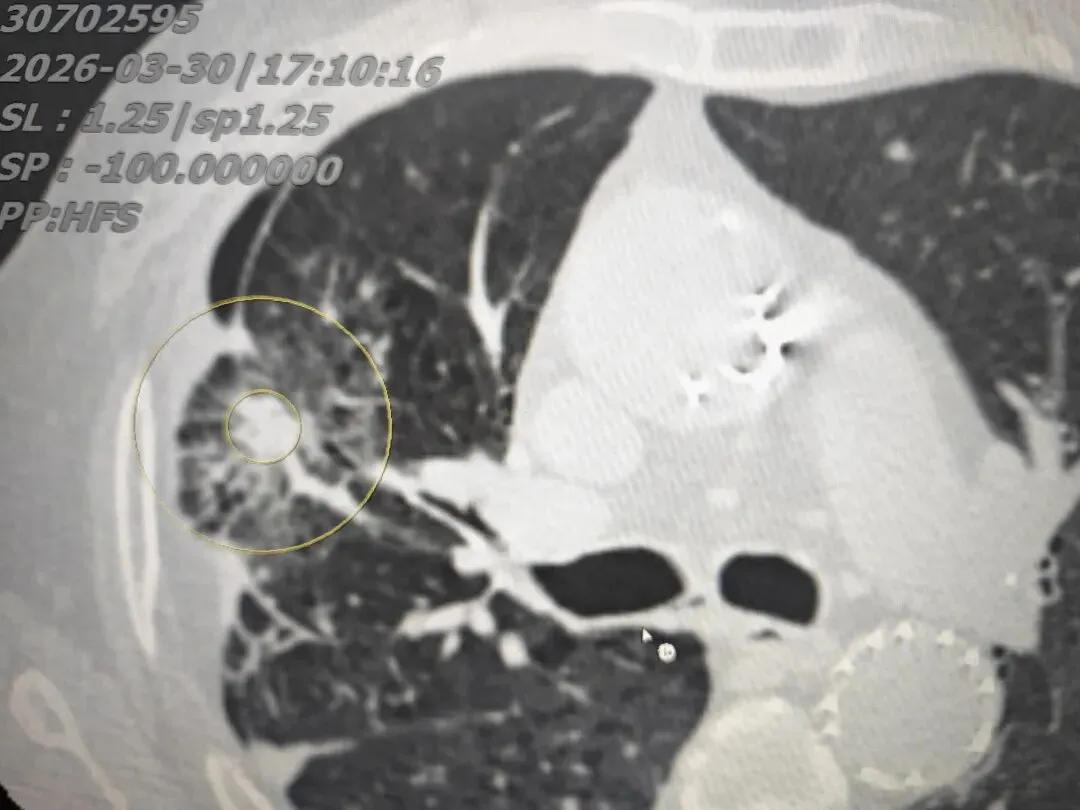

综合评估后,我们为患者选择了肺结节消融治疗。术中将消融针精准穿刺至结节部位,通过针尖产生120~150℃高温,对肿瘤及周边安全范围内组织进行彻底灭活,术后患者恢复顺利。

完美的双环消融范围---荷包蛋